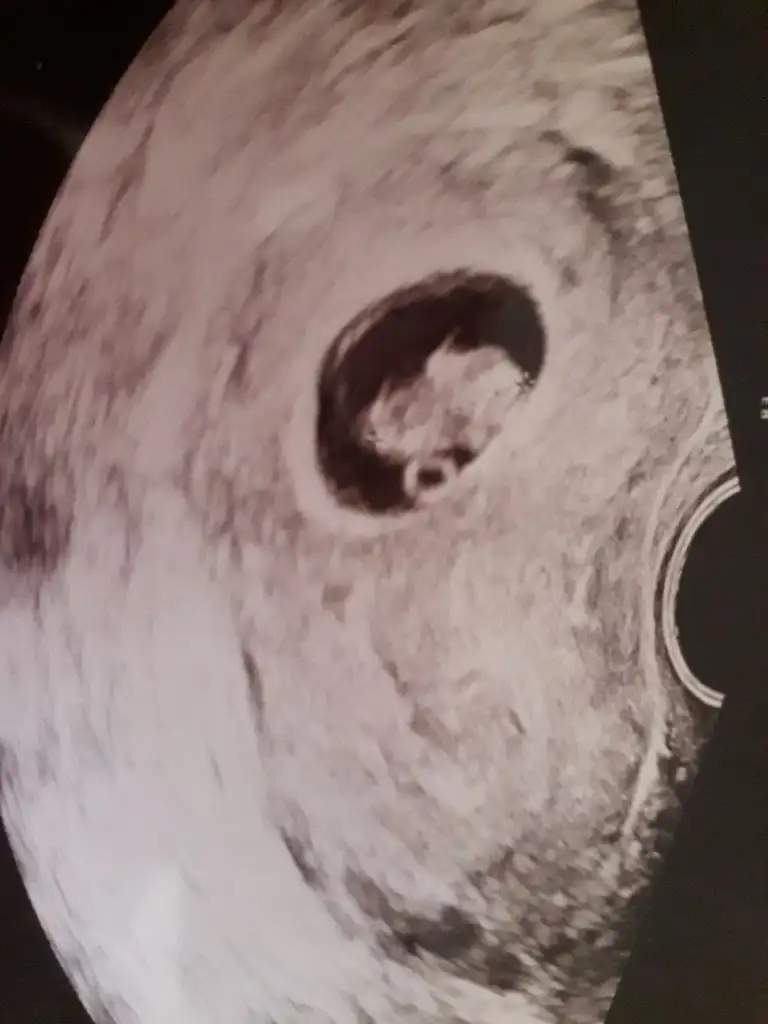

İkiside 7+4. MuBu vajinal 7+4mus 7+5 yazmışız yanlışlıkla

Bu da 7+4 karından usg.

Evet.Ayni gün.Aralarinda saat farkı var sadece.İkiside 7+4. Mu

Burda kız görünüyorEvet.Ayni gün.Aralarinda saat farkı var sadece.

önceki 6+2 USG tahmin ettiğim ama keseye bakmayın nub önemli 11 12 13 haftalar olmalıEvet.Ayni gün.Aralarinda saat farkı var sadece.